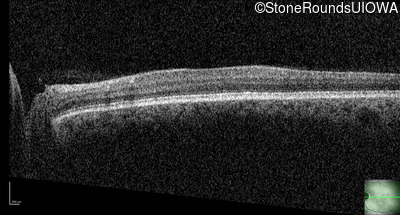

Congenital Stationary Synaptic Dysfunction (IA2g)

Congenital Stationary Synaptic Dysfunction (IA2g)

| Congenital Stationary Synaptic Dysfunction | CABP4 | Arg49Stop CGA>TGA | IVS1+1 G>T | AR |